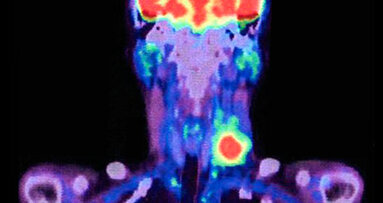

ABERDEEN, Scozia: Il tumore della testa e del collo è una malattia altamente debilitante che comporta conseguenze significative sulla funzione orale, ...

Houston, Columbus e Miami (Usa) ‒ Un team di ricercatori è stato in grado di identificare con precisione il linfonodo sentinella – il primo ...

OSLO, Norvegia: Il tumore della testa e del collo è il settimo gruppo di tumori più diagnosticati a livello globale, e tra le sue modalità di trattamento...